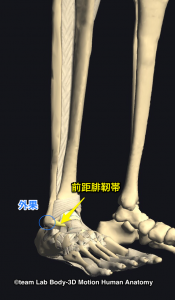

足首の捻挫か骨折か判断 オタワ足関節ルール バッファロールール 鍼灸スポーツ整体アスイク 尼崎 塚口 武庫之荘 伊丹 美容鍼 酸素カプセル パーソナルトレーニングダイエット

足関節捻挫 万々クリニック 公式

足首の捻挫か骨折か判断 オタワ足関節ルール バッファロールール 鍼灸スポーツ整体アスイク 尼崎 塚口 武庫之荘 伊丹 美容鍼 酸素カプセル パーソナルトレーニングダイエット

足首の捻挫で骨折してる してない の判断の指標 高石市東羽衣の阪本整骨院

足首の 捻挫 について Kenspo通信 No 31 健康スポーツクリニック メディカルフィットネスfine